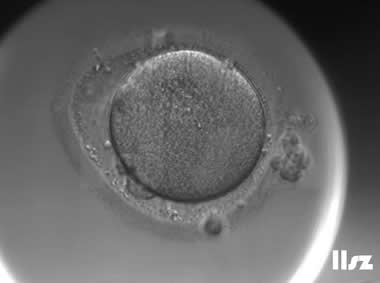

4. 异常卵母细胞及其COCs

该案例中,卵母细胞黄素化,透明带破裂,用酶消化颗粒细胞后仅剩一团变形的胞质。

|  |

| 0小时COCs的异常卵(4x) | 0小时COCs的异常卵(10x) |

|  |

| 2小时COCs的异常卵(10x) | 4小时去颗粒细胞后的异常卵(10x) |